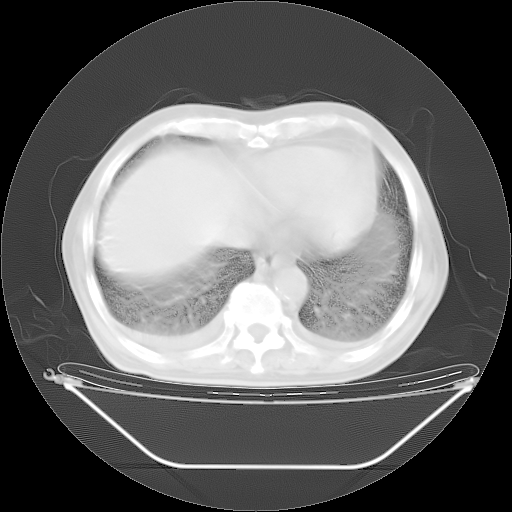

今天复查肺部CT,发现双肺广泛磨玻璃样改变。所以我把3月19日和5月9日相隔50天的肺部CT上传。请大家会诊。

5月9日肺部CT(在4月27日齐鲁医院肺部CT描述部分肺组织磨玻璃样改变,12天后肺组织广泛磨玻璃样改变)

2009年5月9日肺部CT

大致读了系列胸部CT:纵隔窗无明显异常,肺窗:从4、27至今:主要是双肺中下野外带可见毛玻璃样改变,目前处于急性肺泡炎阶段,至于原因考虑1、结替组织或胶原血管性疾病所致?2、恶性疾病如恶组在肺部所致的表现或细支气管肺泡癌?3、药物或其它原因如肺蛋白沉着症所致肺泡炎目前不太可能?总之,明天就去请我院的呼吸科、感染科、血液科和临免专家会诊哈。